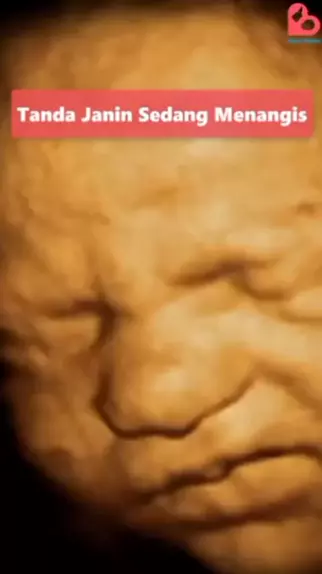

Tanda perkembangan janin gak normal #edukasi#snackvideo#trending#snackstatus

Nah perhatikan baik2 ya Bun #belajar #edukasi #barutau #FISIKA #fakta #utbk #fyp #mikroskop #zoom

Nah ini harus diperhatiin ya Ibun #belajar #edukasi #barutau #FISIKA #fakta #utbk #fyp #mikroskop #zoom